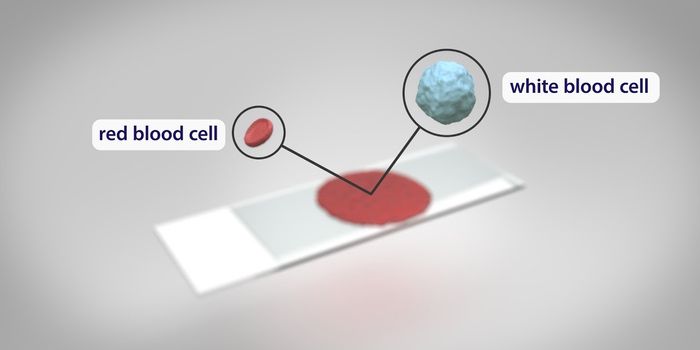

FEB 23, 2019CardiologyThe circulatory system is a complex collection of the heart and its many chambers, and the vessels that move blood aroun ...